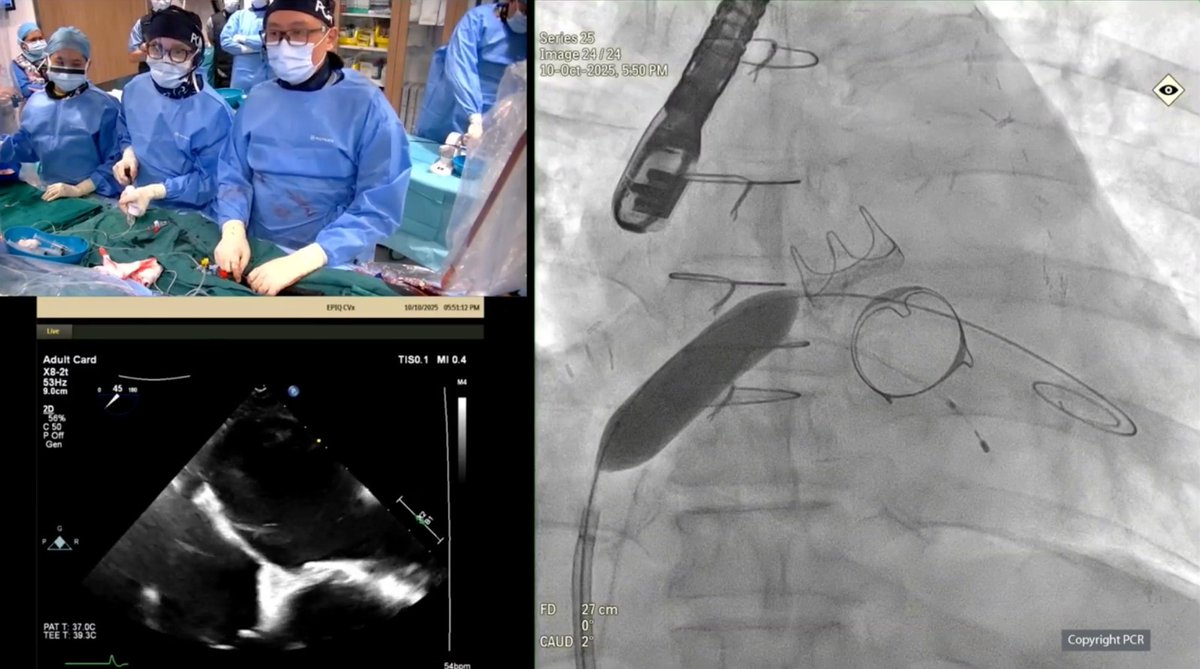

Pushing the frontiers of heart care ❤️ A proud moment for #NUHCS at #AVPlusCONNECT Modern PCI LIVE - Prof Tan Huay Cheem, Senior Advisor, & Dr Christopher Koo, Consultant, successfully performed a complex live heart procedure among 9 global collaborations & 80 live cases. 👏

AICT-AsiaPCR 2025, a major cardiology conference, gathered over 1,000 experts for 2 days of learning. #NUHCS presented 4 complex treatment procedures led by A/Prof Mark Chan, A/Prof Adrian Low, Adj A/Prof Loh Poay Huan, Asst Prof Ivandito Kuntjoro, Dr Gavin Ng & Dr Qian Qi.